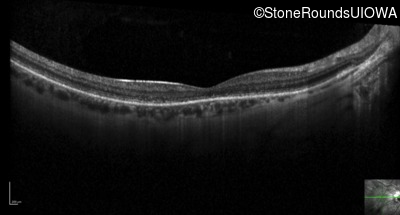

Optical Coherence Tomography - Right - 20/32 -1

Exemplar / OCT Stack

OCT Stack